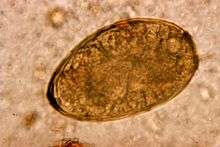

Paragonimiasis, or lung fluke uses cats as a reservoir and subsequently can transmit the infection to humans. Symptoms in cats have not been observed. There are over nine species of lung flukes that can be transmitted to humans from cats. The disease has been found in Asia, Africa, India, North, South and Central America. It is not uncommon and estimates of those infected are in the millions. Signs symptoms in humans are coughing up blood, migration of the flukes into other body organs including the central nervous system. There it can cause neurological symptoms such as headache, confusion, convulsions, vision problems, and bleeding in the brain. This infection in humans is sometimes mistaken for tuberculosis.[8]